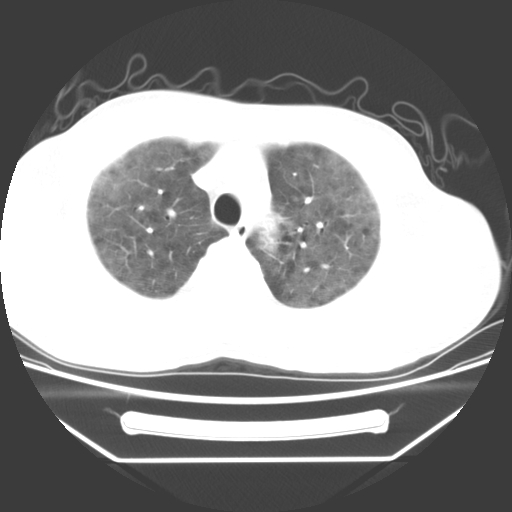

病人55岁,咳嗽,胸闷

忘了传病史了,病人55岁,咳嗽,胸闷

病人是否发烧,两肺“磨玻璃”影,其间见空气支气管征和碎路石征。考虑肺泡蛋白沉着症。

弥漫的病变,肺水肿?

两肺广泛对称磨玻璃样影,密度不均,考虑机遇性肺部感染。

病史提供不详细,肺水肿不能排除,首先考虑肺泡蛋白沉着症

双肺弥漫磨玻璃样病变,病史很重要。有感冒或发烧史,甲流不除外。无发烧可考虑肺泡蛋白沉积,但肺泡蛋白沉积边缘往往较清晰,与正常肺组织分界清晰

两肺弥漫间质性病变,考虑肺泡蛋白沉着症。建议进一步检查。

两肺“磨玻璃”影,其间见空气支气管征和碎路石征。考虑肺泡蛋白沉着症。

此病人我并没有见到,病史没有得到更详细,但此病人据说有发低热,请教各位老师,此病人像不像卡氏肺囊虫肺炎

考虑pcp?不像肺泡蛋白沉着症。